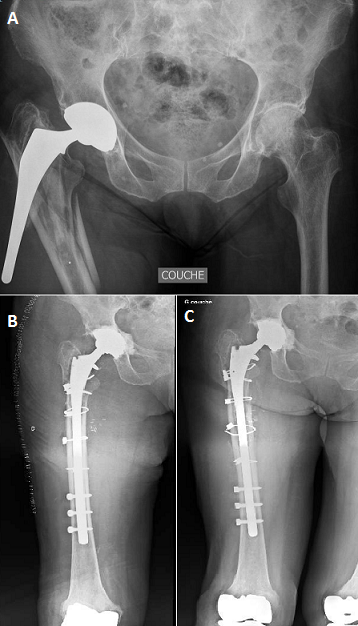

Nous rapportons le cas d'une patiente âgée de 71 ans, victime d'une chute de sa hauteur sur sa hanche droite et dont l'examen clinique objective en plus de la douleur de la hanche d'une hypoesthésie de la face dorsale pied droit avec déficit de la dorsiflexion. Le bilan radiologique montre une fracture trochantéro-diaphysaire complexe avec un descellement important de la tige fémorale qui est presque extériorisée du canal fémoral (A). La patiente a bénéficié à j+1, d'une ablation de la tige fémorale descellée, reconstruction de la fracture par des câbles et neurolyse du nerf sciatique comprimé par la tige puis reprise par une tige longue verrouillée et un cotyle cimenté (B). A 14 mois de recul (C), la patiente marchait avec une canne avec persistance d'un déficit des releveurs des orteils 3/5 et des fibulaires latéraux 3/5.